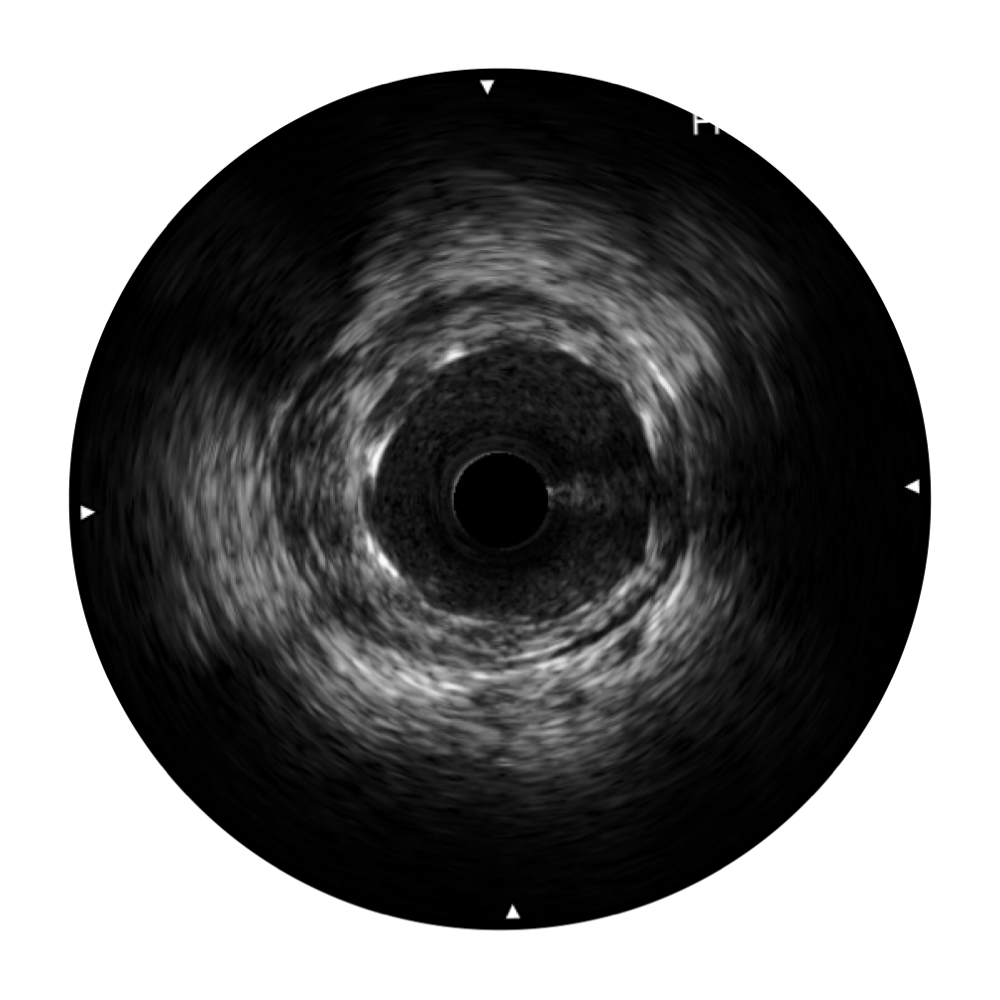

血管内超声(IVUS) 通过对病变程度、性质和累及范围的精确判断,可帮助选择治疗策略和方法,指导介入治疗过程,能够降低主要不良心血管事件,改善预后,在复杂病变介入治疗中用于指导支架置入的优势更为明显。血管内超声(IVUS)已成为精准心血管介入治疗的“金标准”。

对比传统IVUS导管成像,狗万官方网站宽频IVUS图像的近场支架梁显影更细腻,远场中膜外血管仍清晰可辨,兼顾远中近,兼顾分辨力与穿透深度